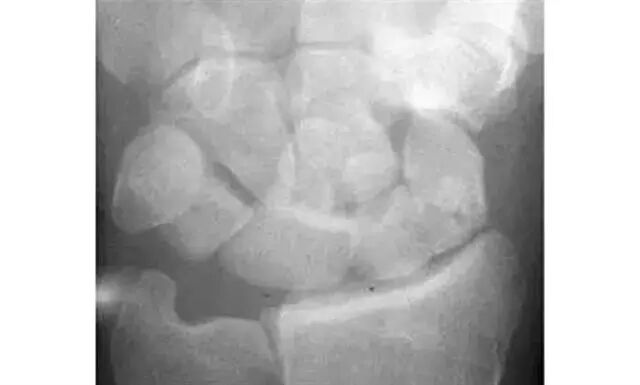

Analyze-腕骨弧线正位弧线不连续,侧位明显脱位。

1.月骨-三角骨间隙不平行,存在重叠。

2.钩状骨和月骨也存在重叠。

3.桡骨、月骨、舟骨近极和头状骨近极平行关系存在。

4.三角骨、钩骨、头状骨远极、大多角骨和舟骨远极平行关系也存在。

5.头状骨和舟骨骨折。

诊断:经舟骨、经头状骨月骨周围骨折-脱位。